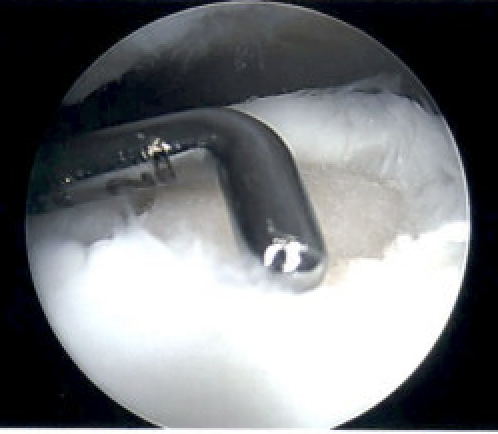

Microfracture

Technique

Arthroscopy techniques microfracture talus